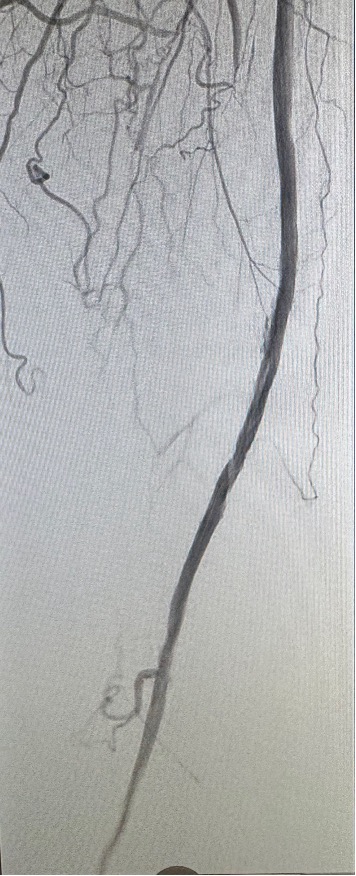

Live @MountSinaiIR ready for #GEST2026 UAE for AVF fertility outcomes to be presented by MS2 mentee @JunnyKim02 . Congratulations on this project and the @SIRspecialists Culp Student Research Grant⭐️⭐️⭐️